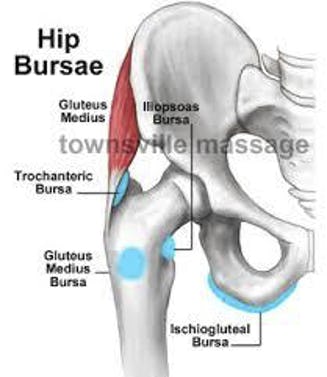

Hip bursitis, also called trochanteric bursitis, affects many people every day. It is characterized by pain and/or stiffness in the hip which is worsened with pressure, and potentially redness and swelling. The pain is caused by inflammation of the fluid-filled sacs, called bursae, which cushion the bones, tendons, and muscles near your joints. Normally part of a cushioning system to ease joint movements, inflamed bursae can make moving quite painful.

The hip is the largest and highest weight-bearing joint in the body, so it’s no wonder inflammation can occur around it. Where the femur (upper leg bone) meets the pelvis, a ball-and-socket joint sits which gives you your range of motion in your hip. It is held in place by large ligaments, muscles, and tendons, and coated in thick cartilage to make your everyday motions easy, and pain-free. However, problems such as trochanteric bursitis can arise and make movements quite painful. Inflamed bursae are further irritated by any hip movements around them, making hip bursitis a debilitating condition, especially for those who are physically active.